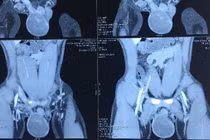

Tại Bệnh viện Đại học Y Hà Nội, bệnh nhân được thăm khám tỉ mỉ và chẩn đoán: Xoắn thừng tinh bên trái ngày thứ hai. Bác sĩ chuyên khoa chỉ định mổ cắt bỏ tinh hoàn vì tinh hoàn đã bị hoại tử.